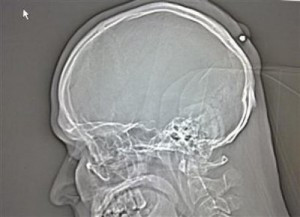

Man, shot in head, notices five years later

Tue Aug 24, 11:47 am ETBERLIN (Reuters) – A Polish man living in Germany went about his business for about five years without noticing he had been shot in the head because he was drunk when it happened. Police in the western city of Bochum said on Tuesday doctors found a .22 caliber bullet in the back of his head after the 35-year-old went to have what he thought was a cyst removed.

Presented with the 5.6mm projectile, the man recalled he had received a blow to the head around midnight at a New Year’s party “in 2004 or 2005,” but had forgotten about it because he had been “very drunk,” a police spokesman said.

The wound later healed around the bullet and it was not until the man decided to have the lump examined due to recurring pains that the discovery was made.

Police said they were not treating the incident as suspicious as the bullet might have got lodged in the man’s head when a reveler fired a gun in celebration.

“It may have been a shot fired up in the air which entered his head on the way down,” the spokesman said.